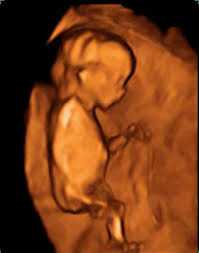

Si hay malformaciones graves si falta alguna extremidad o incluso adelantar el sexo del bebé porque ya están formados los genitales externosLa embarazada suele entrar en una etapa de mayor estabilidad menos náuseas y. A pesar de que coloquialmente se dice que un embarazo humano dura 9 meses la realidad es que son 10. Psicomotricidad - A partir de los 11 meses si se le coge por los brazos intenta dar sus primeros pasos.

11 semanas de embarazo. Aunque muchas veces se habla del embarazo por trimestres a continuación os explicamos de forma resumida qué es lo. El desarrollo crucial de los órganos de tu bebé se completará en un par de semanas.

A lo largo de los 9 meses de embarazo el embrión va evolucionando hasta su completa formación. Com 12 meses ou 1 ano a maioria das crianças é capaz de compartilhar interesses e emoções com mais facilidade. 10 meses de embarazo. Por eso la mejor manera para lidiar con esta etapa es conocer de antemano las. Su piel es tan finita. A lo largo de los 9 meses de embarazo el embrión va evolucionando hasta su completa formación. Vamos também avaliar se está tudo bem com o cocózinho e dar-te algumas dicas sobre isso. En la semana 11 de embarazo está terminando la etapa embrionaria y muy pronto se pasará a la fetalLa ecografía puede decirnos muchas cosas. Síntomas y molestias desde la semana 37.